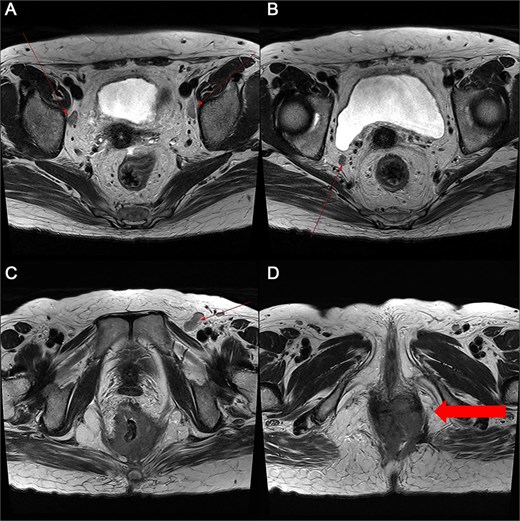

Marked reduction in the size of the tumor and lymph nodes following CCRT.